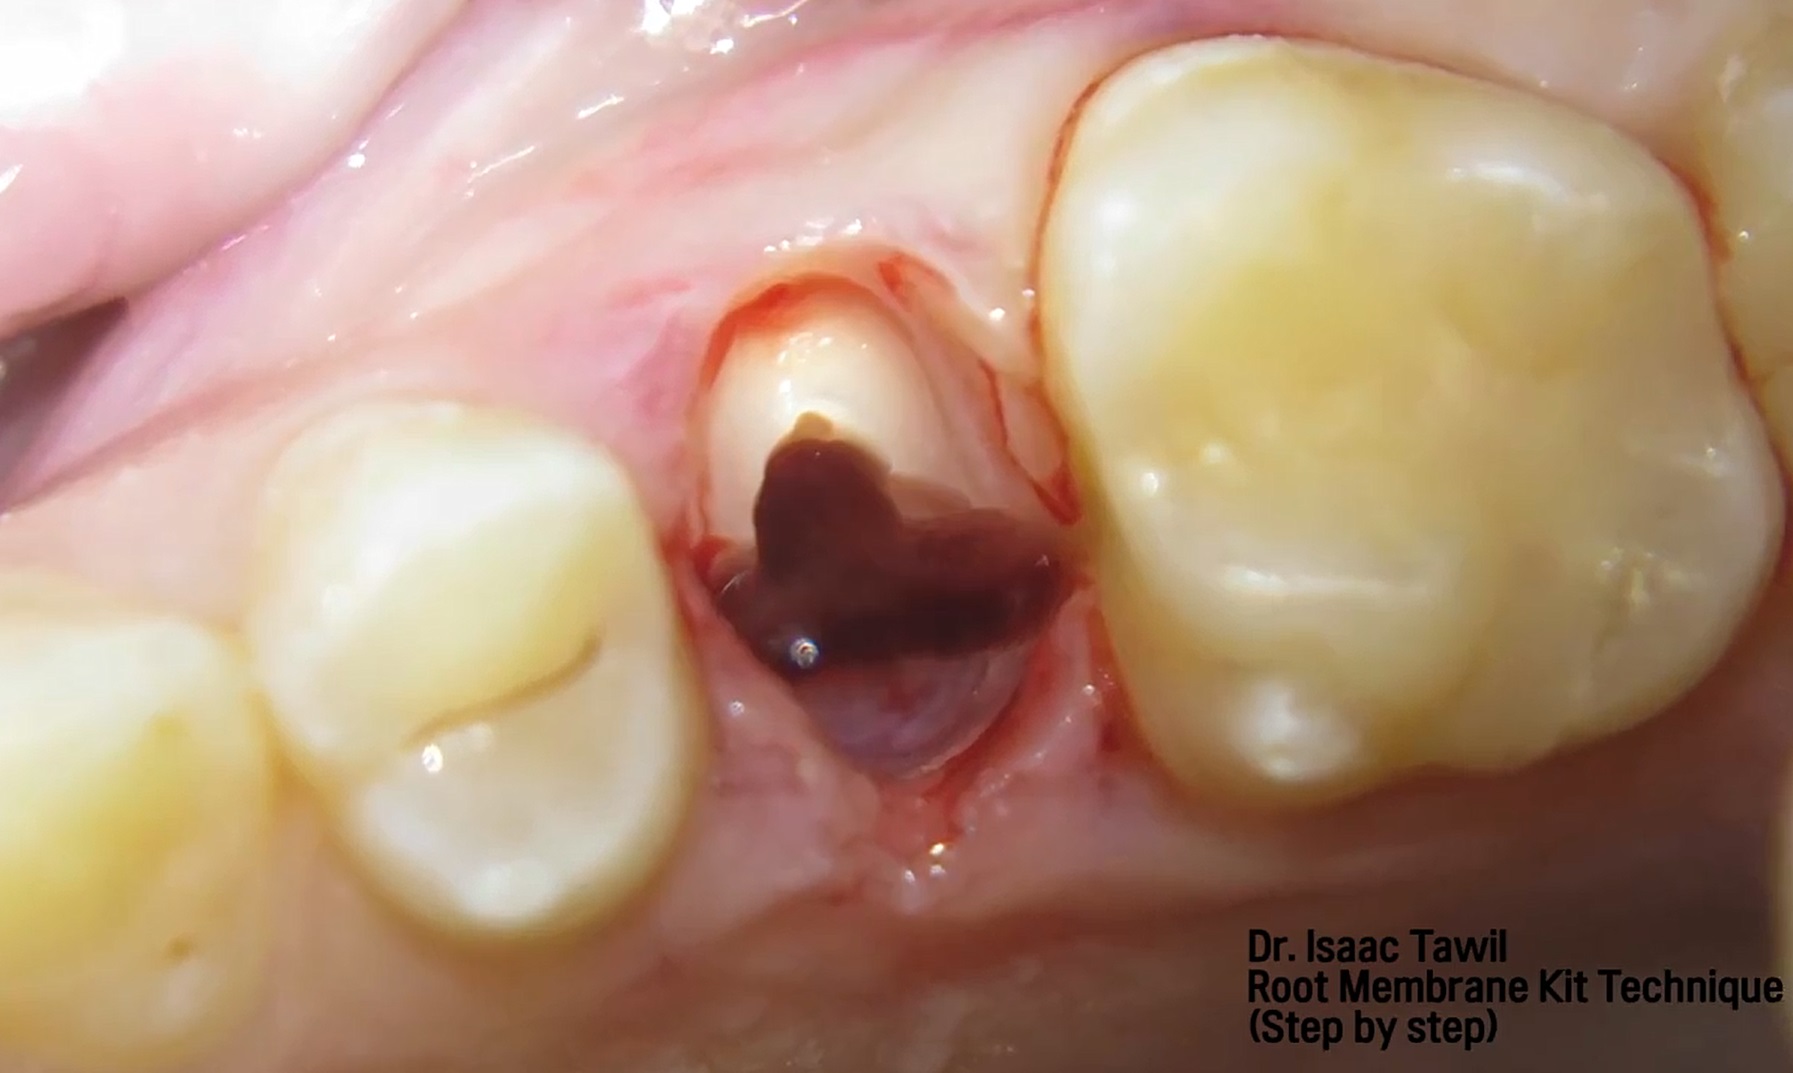

Root Membrane with R2GATE

Dr. Konstantinos Siormpas,Aesthetic Zone,Immediate loading,Digital,Bone regeneration,Maxillary Anterior,#12,#21,#23,Implant Placement,Guided surgery,Immediate loading,Flapless,Root Membrane,GBR,AnyRidge,MEGA ISQ,Root Membrane Kit,Video